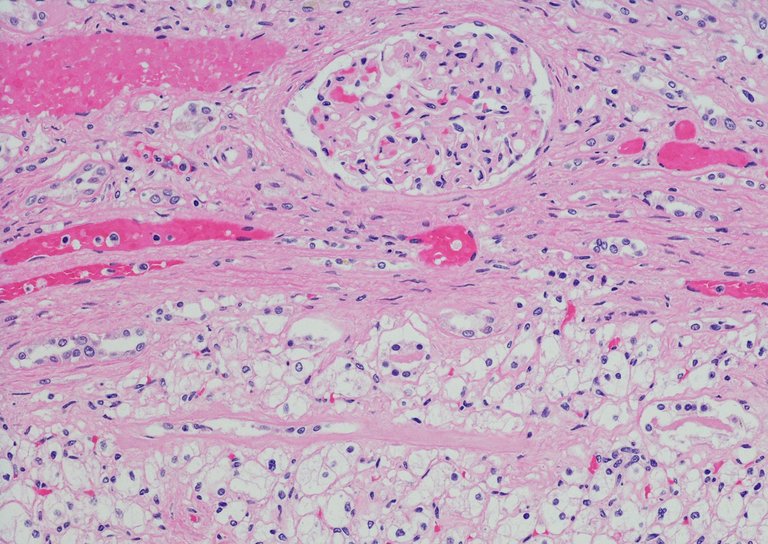

Dans le carcinome rénal à cellule claire, très agressif, il a utilisé la théorie du jeu pour étudier les interactions bilatérales entre les cellules dans deux scénarios différents: l'un est de faible hétérogénéité tumorale puisque seulement deux types de cellules tumorales sont en concurrence pour une ressource; l'autre est de grande hétérogénéité tumorale, car cette concurrence se produit entre trois types de cellules tumorales. Ainsi, il a montré que certains des fondements de l'hétérogénéité intrahumorale, confirmés du point de vue histopathologique et génomique, sont basés sur les mathématiques.